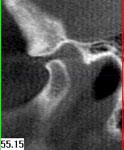

Im folgendem sehen Sie die Darstellung eines Teils des menschlichen Schädels mit Lokalisation des Nervkanales.

Sagittalansicht |